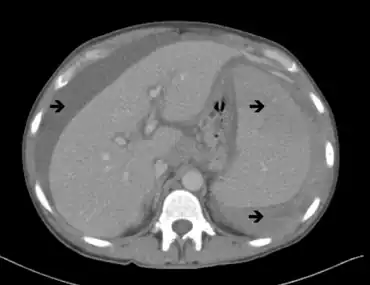

Additional tests such as computed tomography (CT or CAT) scan may be used to evaluate the chest, abdomen, and pelvis, particularly swelling of the lymph nodes, liver, and spleen. A skeletal survey can help distinguish between Waldenström macroglobulinemia and multiple myeloma.[50] Anemia occurs in about 80% of patients with Waldenström macroglobulinemia. A low white blood cell count, and low platelet count in the blood may be observed. A low level of neutrophils (a specific type of white blood cell) may also be found in some individuals with Waldenström macroglobulinemia.[49]